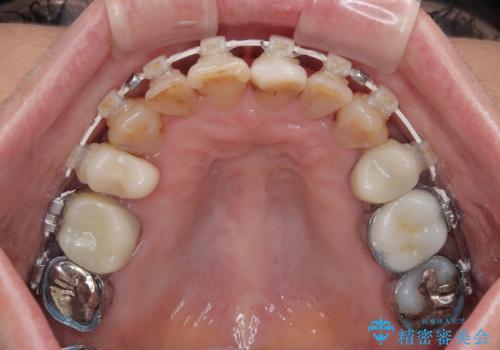

- 長年気にしていた捻れた前歯が欠けたとのことで来院された患者様です。

矯正治療に抵抗があったそうですが、前歯が欠けたことをきっかけに、矯正治療で歯列を整えた上で、セラミッククラウン治療を行う決心が付いたとのことでした。

デコボコが強いため、ブリッジや残根となっている部分のスペースを利用して歯列を整え、変色や欠けている歯をオールセラミッククラウンによる補綴治療を行うこととしました。